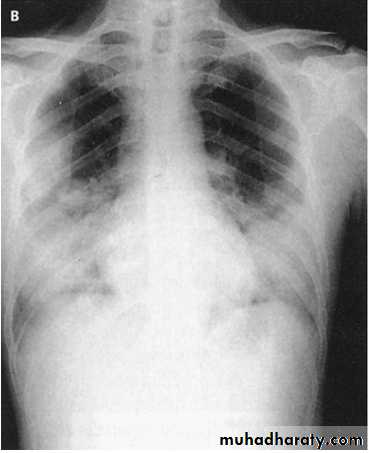

Lobar pneumonia; is a radiological and pathological term referring to homogeneous consolidation of one or more lung lobes, often with associated pleural inflammation

In lobar pneumonia, a homogeneous opacity localized to the affected lobe or segment usually appears within 12-18 hours from the onset of the illness.If a complication such as parapneumonic effusion, intrapulmonary abscess formation, or empyema is suspected.

Clinical-radiographic dissociation is seen often in patients with Mycoplasma pneumoniae or viral pneumonia.

Lateral radiographs are especially important in showing infiltrates, which may be obscured by the heart on posteroanterior projections.